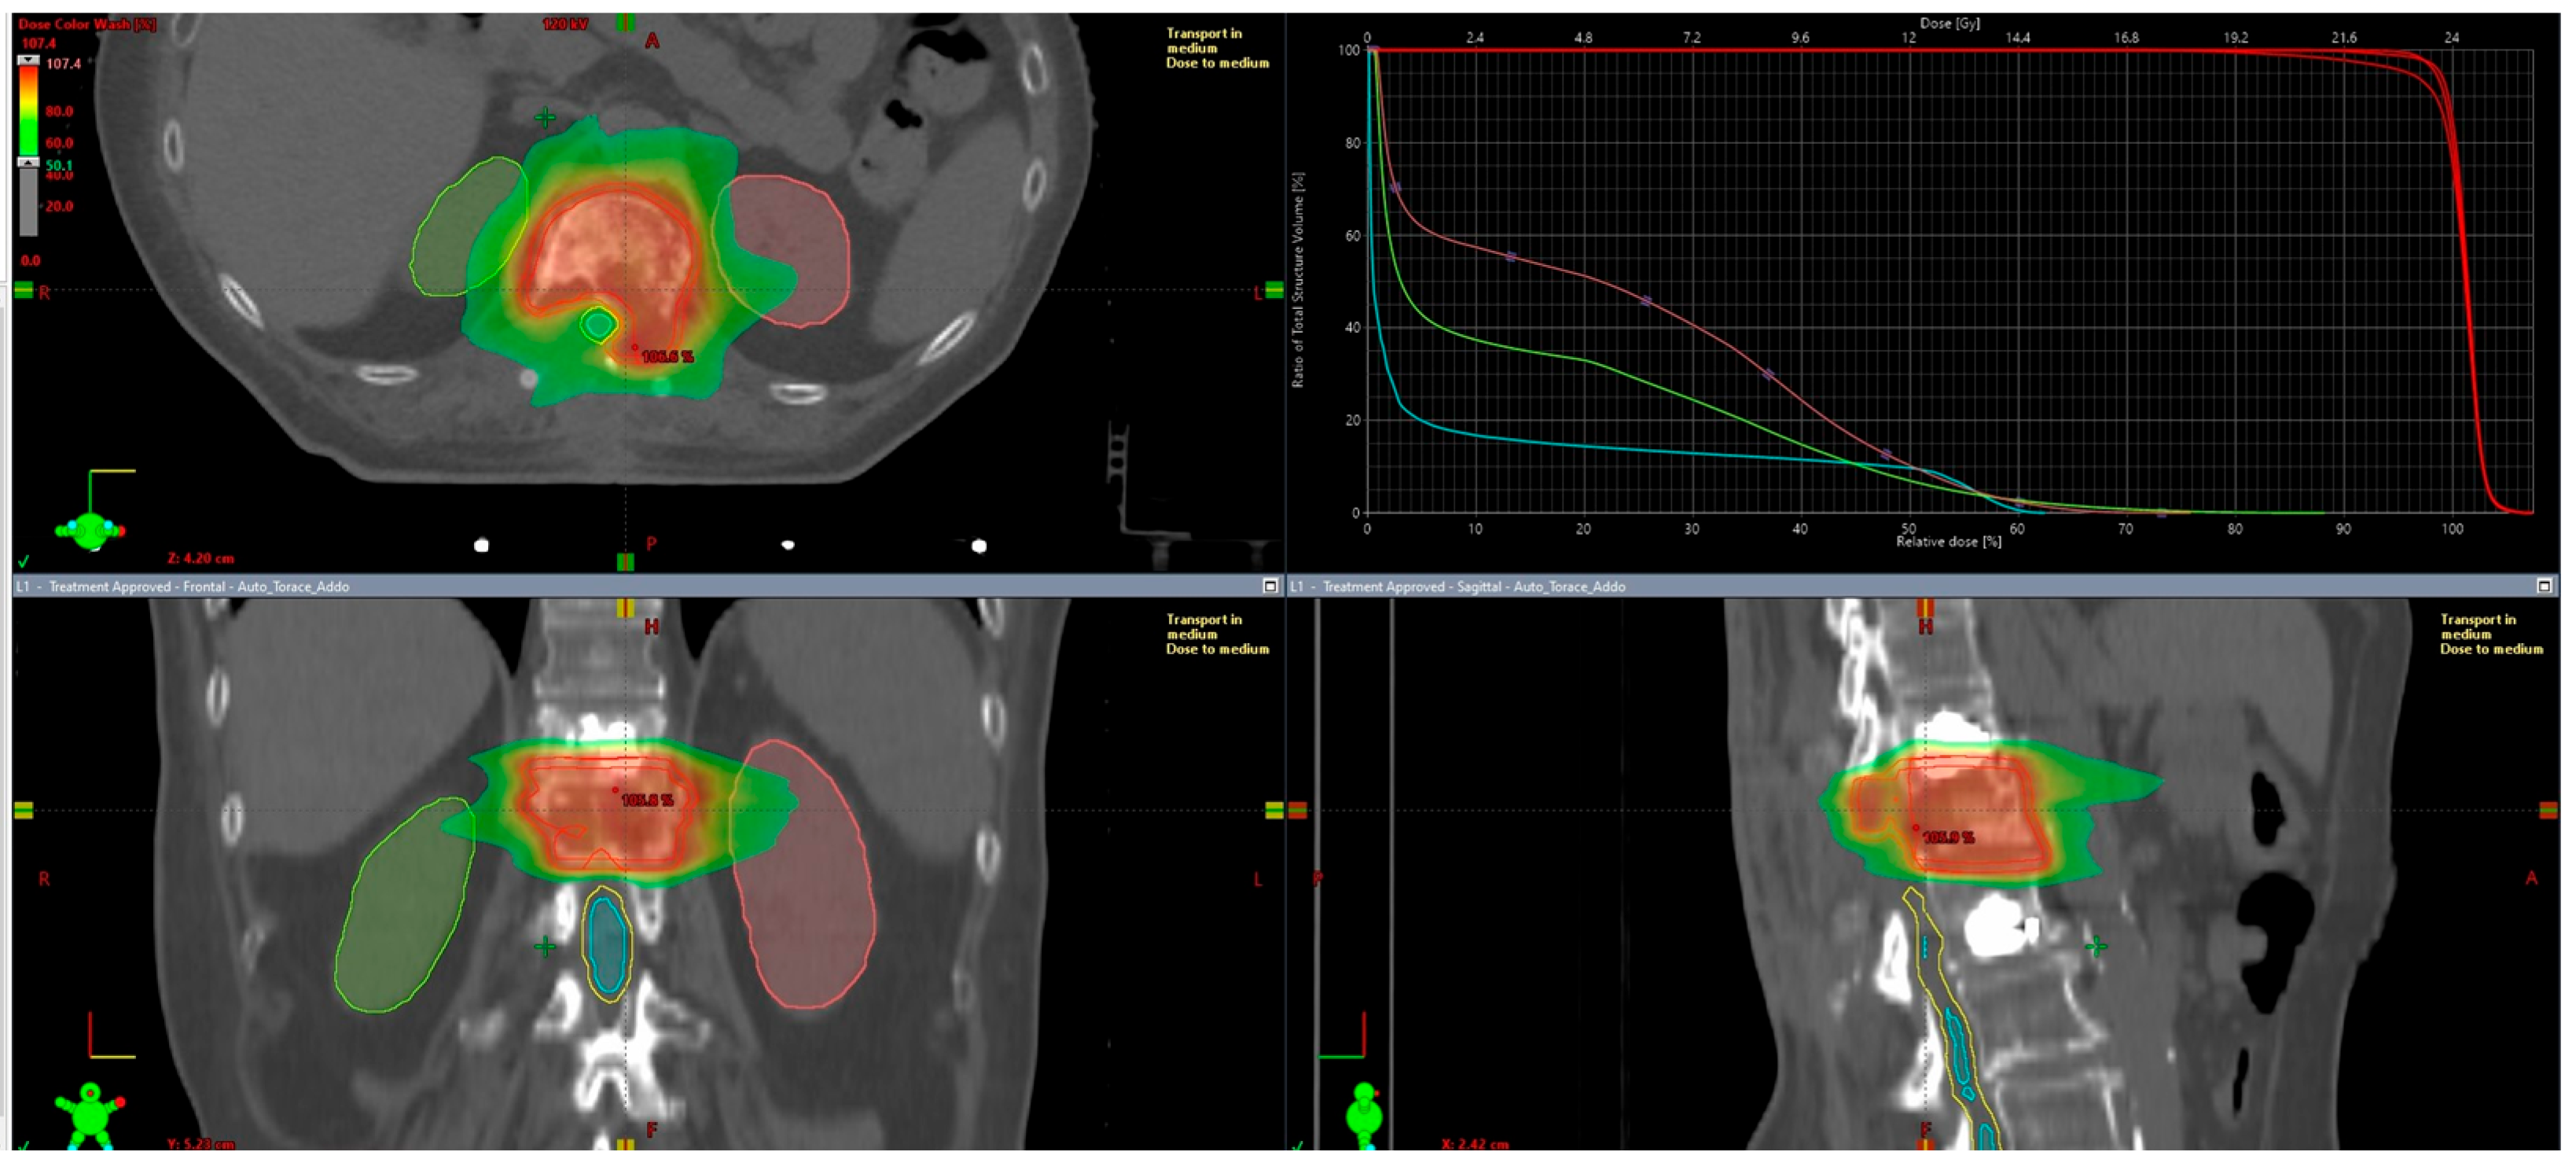

| ORGAN | Constraints to Be Respected | Treatment Specifics |

| PRV Spinal Cord | D0.035 cc ≤ 17 Gy (mandatory) Dmax: ≤17 Gy (optimal) ≤19.3 Gy (mandatory) | D0.035 cc = 16.47 Gy Dmax = 18.31 Gy |

| Small Bowel | Dmax ≤ 20 Gy | Dmax = 12.03 Gy |

| Single Kidney | Dmax ≤ 26 Gy Dmean ≤ 6 Gy | Dmax (left) = 18.2 Gy; Dmax (right) = 21.19 Gy Dmean (left) = 5.39 Gy; Dmean (right) = 3.64 Gy |

| Liver | Dmean as low as reasonably possible | Dmean = 1.19 Gy |

| Target Coverage | V95% > 95% | V95% = 99.6% |